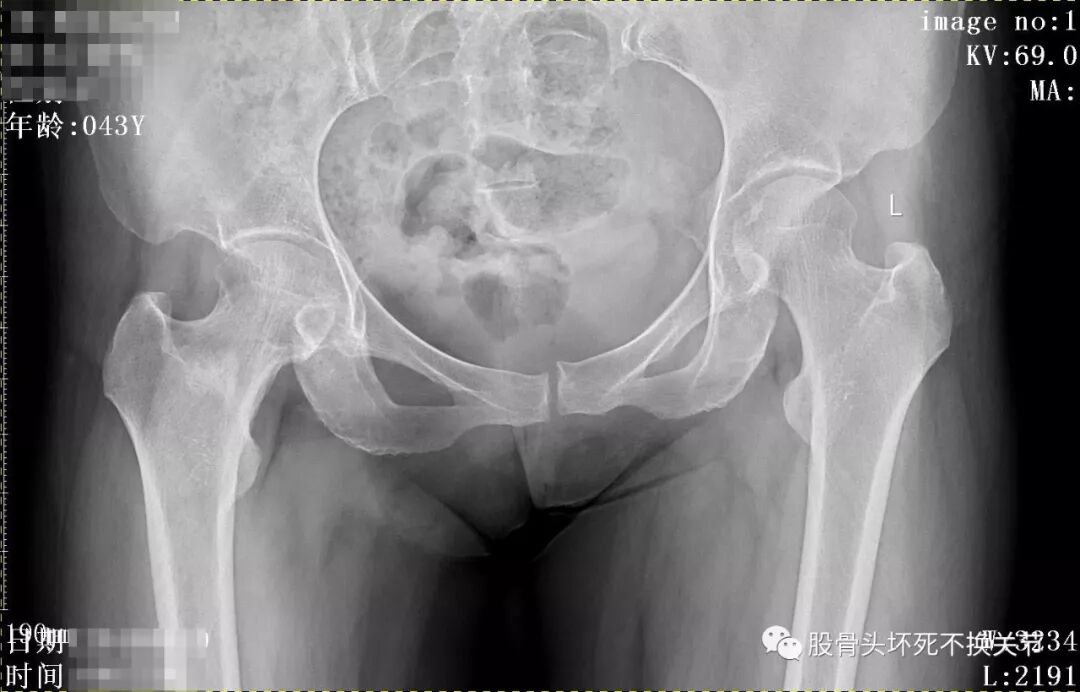

先看一下X光片:

骨盆正位片

从这些歪斜的X线片子可以看到,双髋关节并无特殊表现,双侧骶髂关节似乎轻微硬化(对于42岁生过孩子的女性来讲,不首先考虑病理原因);仔细研判放大了的右髋关节正位、蛙位片,可发现股骨头边缘轮廓并不是特别光整,与对侧相比右侧股骨近端整体骨密度低于对侧,对于一个长期患病、缺乏活动的关节来讲,不足为道,很常见。